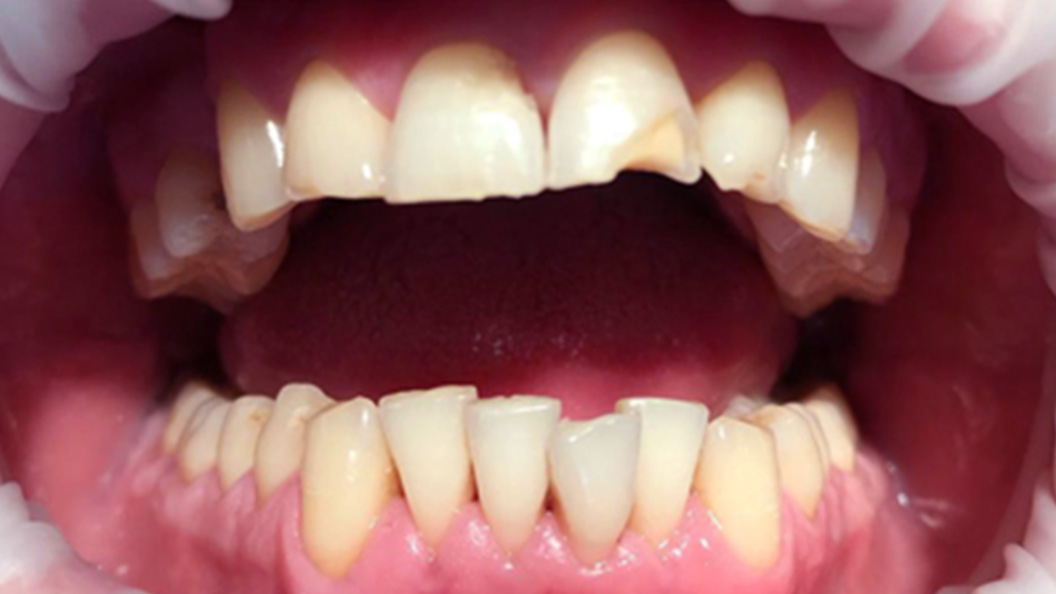

До и после лечения

В нашу клинику обратился пациент с жалобами на дискомфорт из-за неудовлетворительного внешнего вида верхнего резца. Осмотр проводил врач-терапевт Вахлюева Елена Сергеевна.

После оценки состояния полости рта и диагностики Елена Сергеевна рекомендовала проведение реставрации с использованием высокоэстетичного композитного материала.

Реставрация композитным вариантом — быстрый и доступный способ восстановления эстетики улыбки. Проводится прямым методом непосредственно во рту пациента всего за 1 визит. Для восстановления используются качественные пломбировочные материалы, соответствующие естественному оттенку эмали. Они послойно наносятся на зуб и отвердевают под воздействием света.